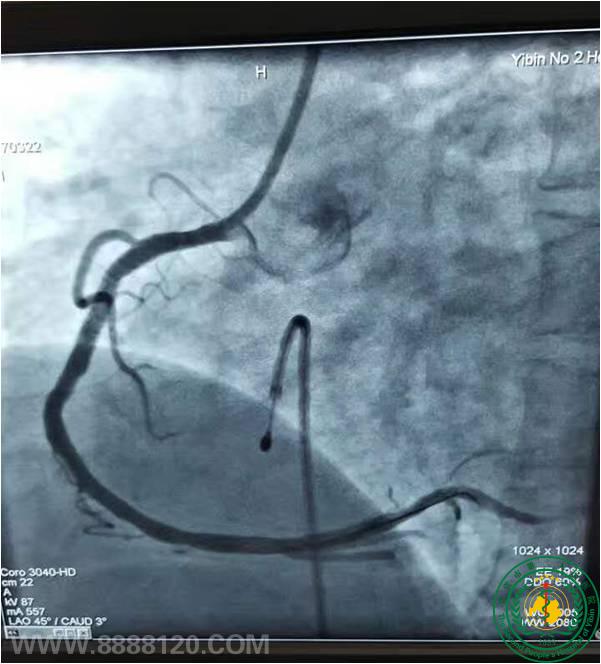

2017年3月21日下午5时,一位来宜出差的41岁患者突发心肌梗死被急诊送入我科,心源性休克、心动过缓,大小便失禁。没有亲属陪同、来不及交费。生死攸关,在和家属短暂电话沟通后,患者被紧急送入导管室……临时起搏加冠脉介入,一刻钟内闭塞的血管被打通……一个年轻的生命在劫难中再获新生、一个行将崩溃的家庭得以救赎……感谢同事们的协作,让微弱的生命火花重放异彩,这是医者存在的价值,我们累并快乐着!